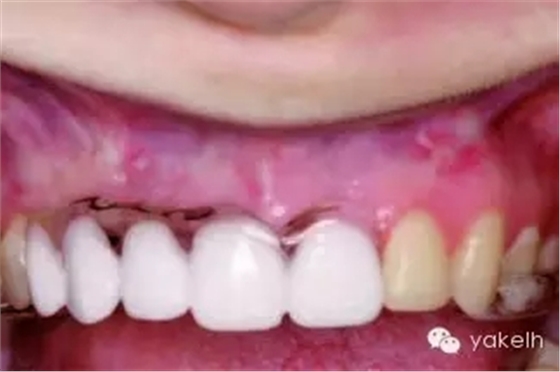

¤¤許多上頜竇以及Onlay植骨的移植物來自于下頜骨頦部。已有報道從下頜骨前牙區(qū)獲取塊狀骨以及顆粒狀骨的技術(shù)。頦部是口內(nèi)能提供最大骨量的區(qū)域(圖13.15)。兩頦孔間的平均距離為5cm,平均厚度為1cm。CT掃描以及全景片能夠評估該區(qū)的可供骨量。頭影測量片可測定下頜骨前牙區(qū)的前后徑。根尖片能更精確地測量牙根長度。

圖13.15 干燥的標(biāo)本提示,從下頜骨頦部可以獲取大量的骨質(zhì)。